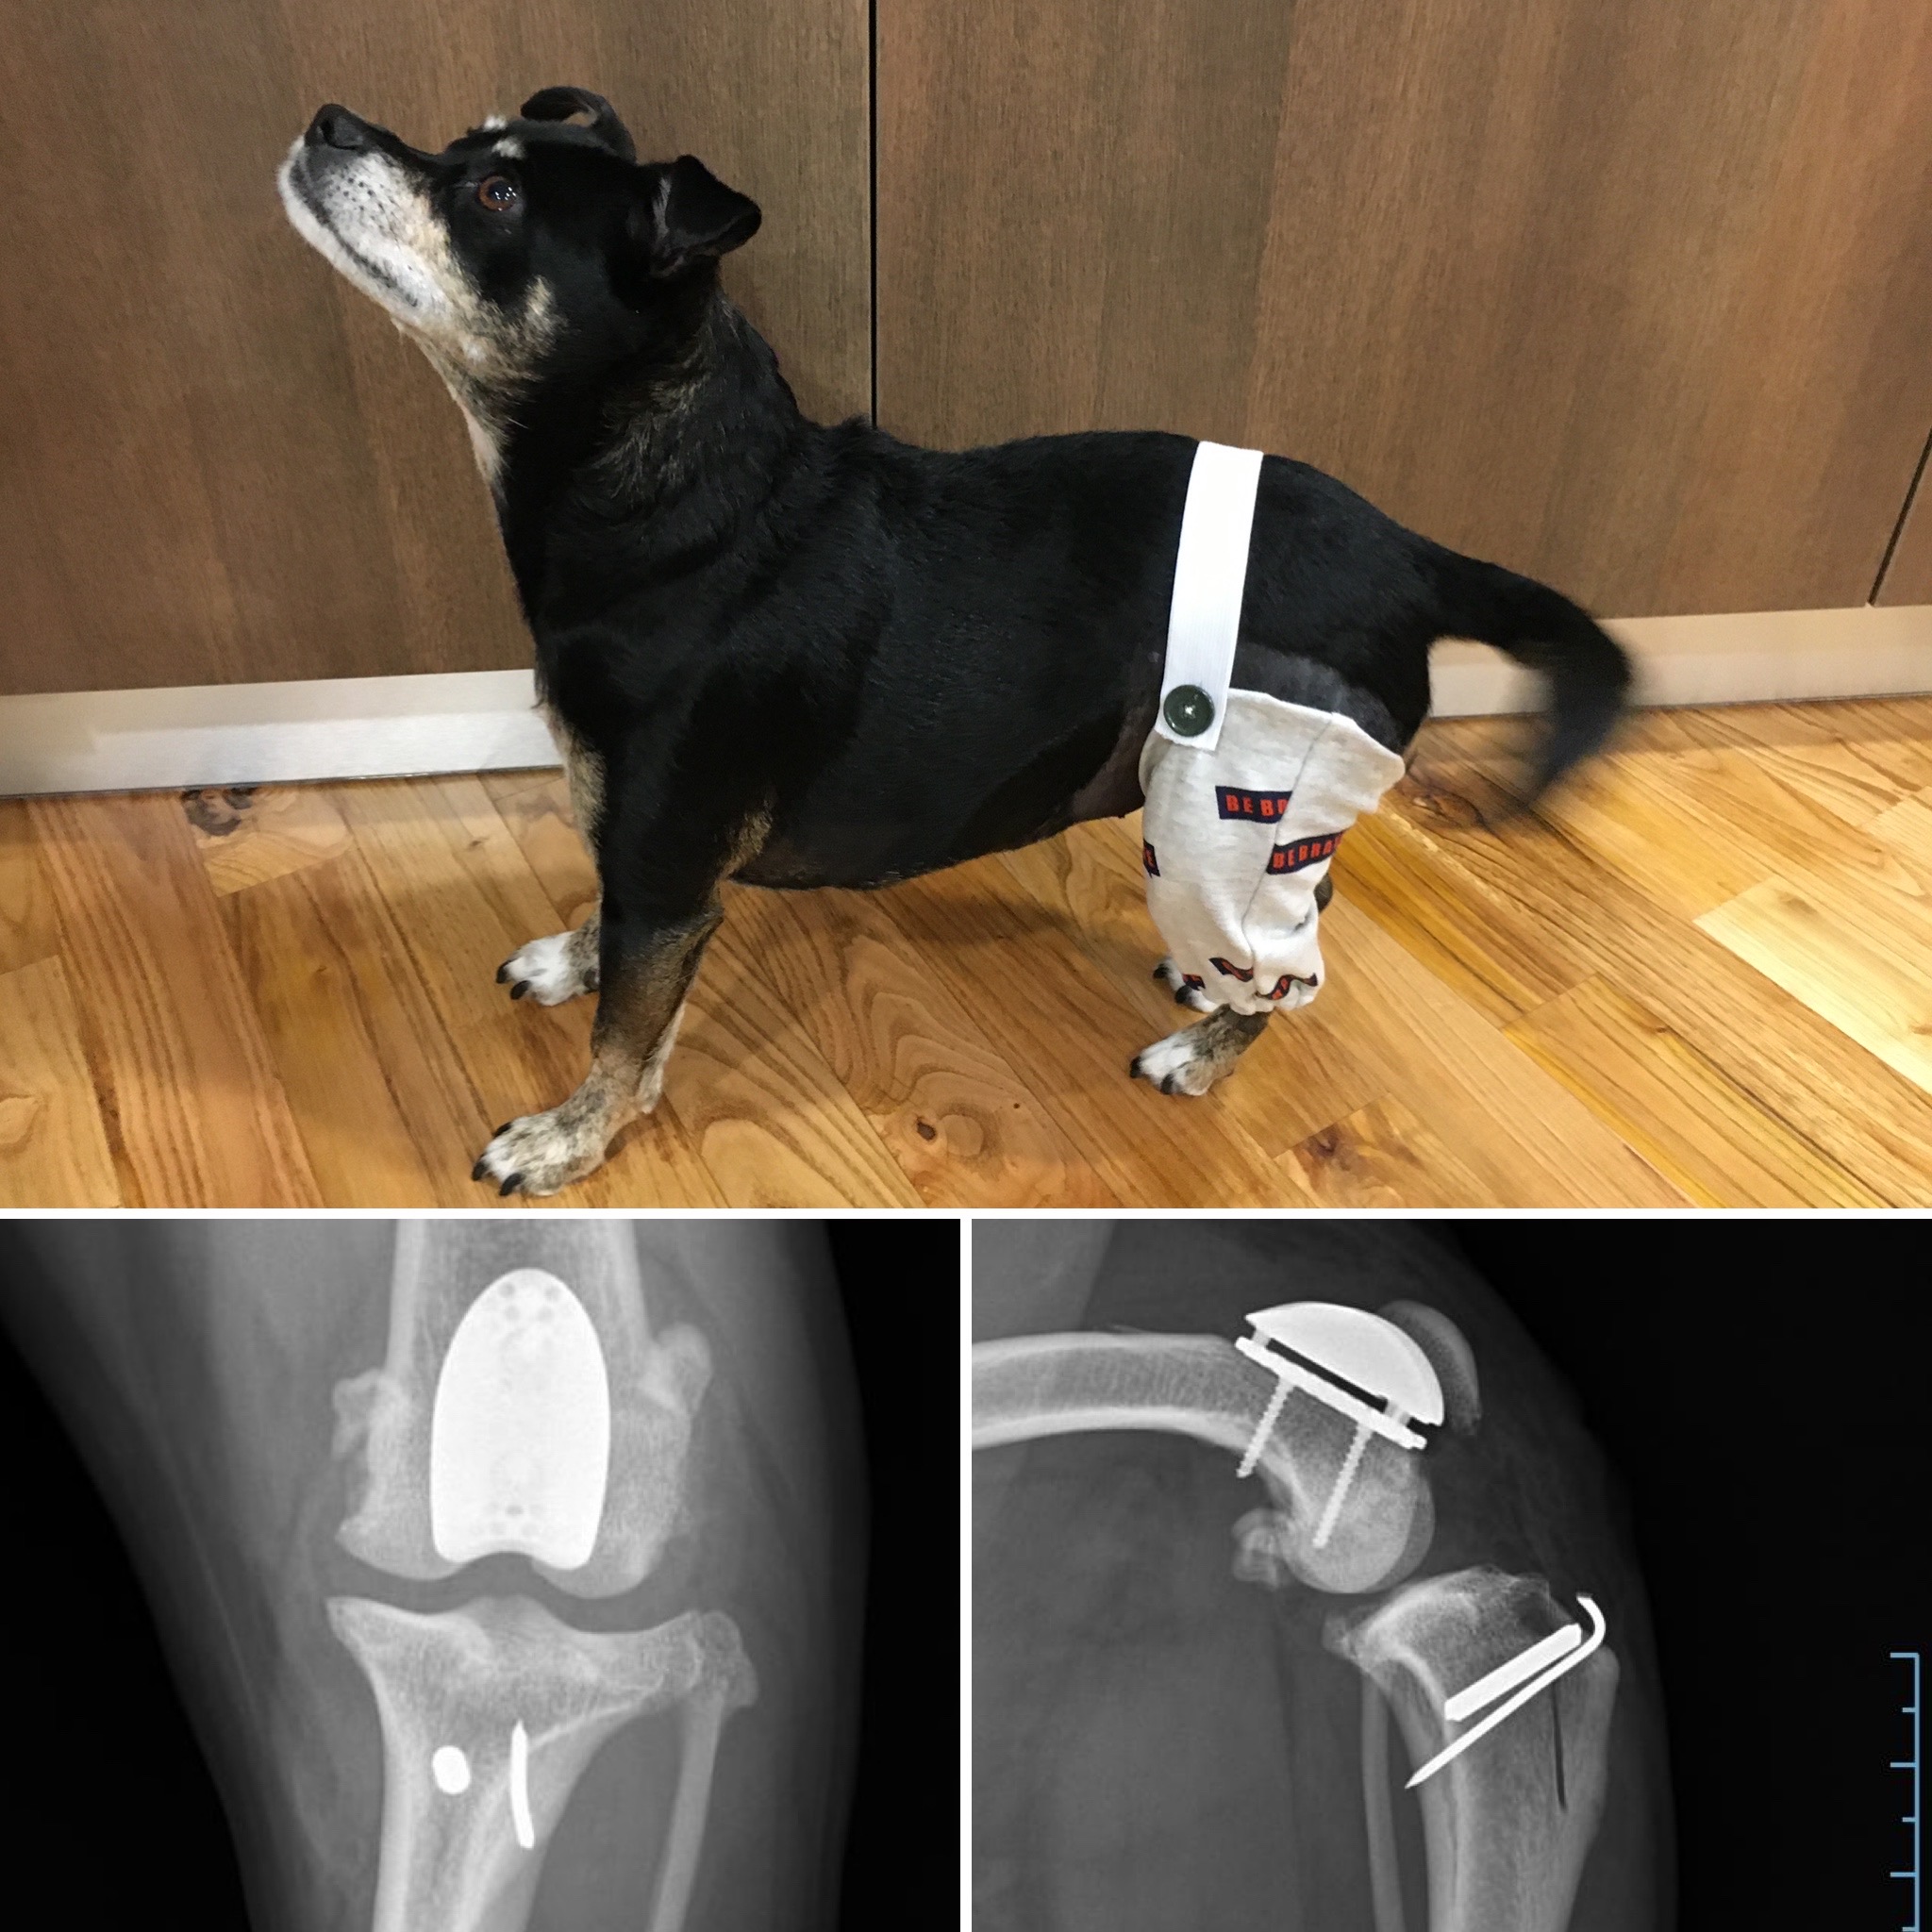

Solução desenhada por tutora para evitar colar isabelino